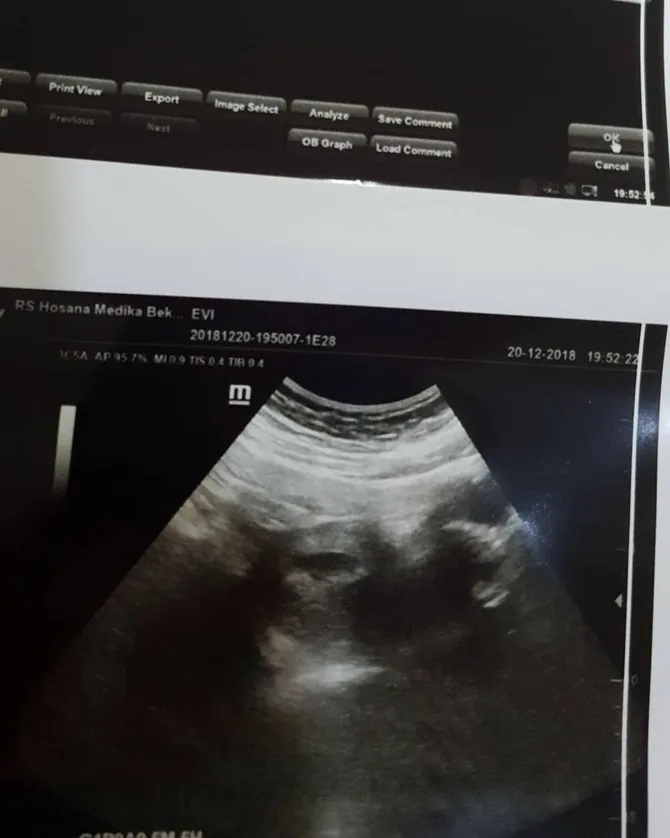

Baru-baru ini Evi sedang memeriksakan kandungannya. Tak lupa ia juga mengunggah hasil USG.

Dari hasil yang terlihat, kondisi kandungan pedangdut bersuara merdu ini dalam kondisi yang sehat. Oleh karena itu ia langsung mengucap syukur. Evi rupanya juga tak bisa menahan rasa sayangnya terhadap sang anak.

"Ya Allah sungguh luar biasa pemberianmu ini. Ada dede kecil di dalam perut aku. Sehat ya nak. Love you. Kamu pasti kuat," ujar Evi Masamba.